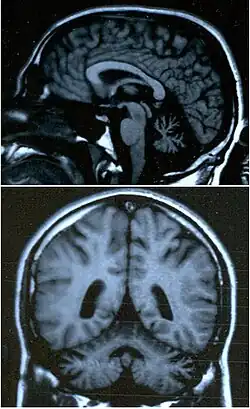

Ataxia (do grego ατάξις, sem coordenação), ou distaxia, é um transtorno neurológico caracterizado pela falta de coordenação de movimentos musculares voluntários e de equilíbrio. É normalmente associada a uma degeneração ou bloqueio de áreas específicas do cérebro e cerebelo.

- Ataxia cerebelar: Causada por danos às vias cerebelares, resultam na perda de coordenação motora e planejamento dos movimentos. Os sintomas dependem da área do cerebelo afetada.

O cerebelo é responsável por uma série de comandos centrais tendo papel de destaque na elaboração, aprendizagem e execução da motricidade. Os possíveis sintomas incluem: